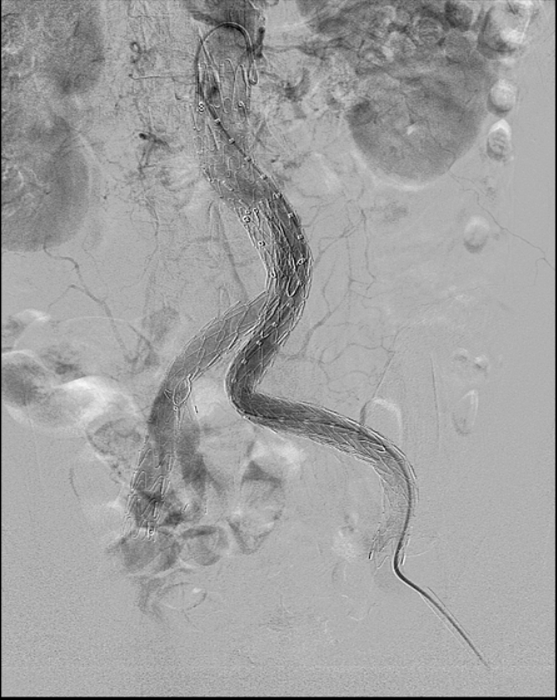

近日,文山州人民医院胸外科心脏大血管外科首次引进G-iliac髂动脉分叉支架系统,为一位68岁的腹主动脉瘤、双髂总动脉瘤患者,成功施行州内首例“腹主动脉瘤、左髂总动脉瘤覆膜支架腔内隔绝、右侧髂总动脉瘤覆膜支架腔内隔绝+右侧髂内动脉分叉支架重建术(IBD支架置入术)”。目前患者术后恢复良好,已康复出院。

腹主动脉瘤可同时累及单侧或双侧髂总动脉,髂内动脉受累及是孤立性髂动脉瘤和腹主动脉瘤合并髂总动脉瘤病变中的常见现象,采用腹主动脉瘤腔内修复术治疗时,需要考虑保留或牺牲髂内动脉的问题,在施行累及髂动脉瘤的支架手术时,经常需要栓塞或闭塞髂内动脉,封堵髂内动脉后可能带来相应的并发症,如:臀肌缺血萎缩、跛行、性功能障碍、结肠缺血、脊髓缺血、臀肌或直肠坏死等。采用G-iliac髂动脉分叉支架系统,适用于腹主动脉瘤合并髂动脉瘤或孤立性髂总动脉瘤的患者,保障患者的髂内动脉血流通常,减少并发症的发生。

文山州人民医院胸外科心脏大血管外科自2008年开展腔内介入手术以来,经过多年的成长,目前已常规开展胸腹主动脉夹层、胸腹主动脉瘤、髂动脉瘤的腔内介入手术治疗。此次G-iliac髂动脉分叉支架重建手术(IBD支架置入术)的成功开展,标志着医院在心血管外科领域更上新台阶,同时能为全州的患者提供更优质的服务。